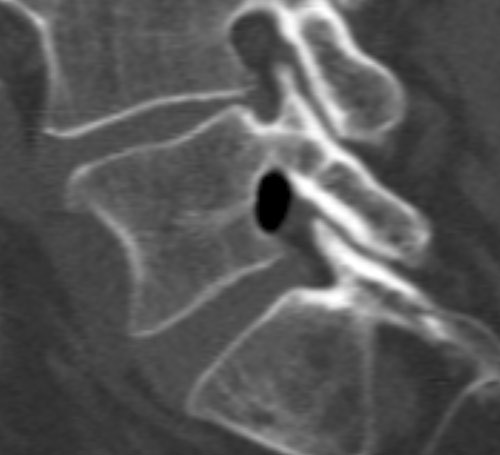

En mann i 60-årene ble innlagt med to dagers sykehistorie med venstresidig isjialgi og pareseutvikling i L5-innervert muskulatur. MR viste en oppfylling i venstre laterale recess i nivå L4/L5 med dorsal dislokasjon av venstre L5-rot. Oppfyllingen hadde uvanlig lavt MR-signal som ga mistanke om forkalkninger eller luft. Supplerende CT viste en velavgrenset luftansamling i samme område (bildene).

Klinisk forverring førte til kirurgisk eksplorasjon av L5-roten. Ventralt for denne så man en luftmengde innkapslet i epiduralt bløtvev, incisjon ble foretatt og luften sluppet fri. Etter dette var L5-roten mykere palpatorisk og hadde fritt forløp. Pasienten opplevde betydelig bedring postoperativt.

Hos vår pasient forelå bare lettgradig skivebukning uten ruptur i anulus fibrosus og lett fasettleddsartrose i aktuelle nivå. Luften kan representere gassomdanning av et sekvester fra en tidligere prolaps, alternativt pseudocyste assosiert med vakuumfenomen i tilstøtende skiverom. Det er vanskelig å forklare akutt innsettende sykehistorie på bakgrunn av dette, men incisjon og frigjøring av luftansamlingen hos pasienten var likevel terapeutisk.